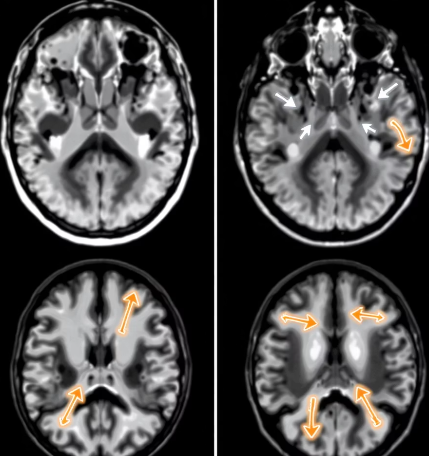

MRI나 CT 같은 영상검사는 기본이지만, 두 질환의 진단에서는 검사의 해석과 병력 청취 방식도 달라집니다.

• 혈관성 치매는 뇌경색 흔적이나 백질 변화가 영상에서 나타남

• 알츠하이머는 조기에는 영상에 큰 변화가 없을 수 있음